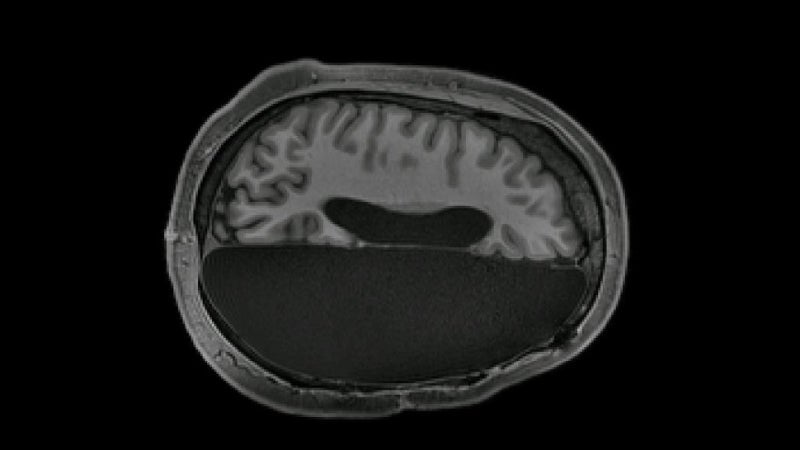

Pasaron varias décadas hasta que dos investigadores del MIT, Patrick Wall y Ronald Melzack, propusieron lo que llamaron la teoría de la compuerta, la cual se mantiene (más o menos) hasta el día de hoy. Esta afirmaba que los estímulos no dolorosos cierran las “puertas” al estímulo doloroso, evitando que la sensación de dolor viaje al sistema nervioso central.

En esencia, su investigación demostró que sentir dolor es más un equilibrio de estímulos en los diferentes tipos de fibras nerviosas. Varios años después, en 1996, la teoría se desarrolló con el neurofisiólogo Edward Perl. El investigador descubrió que las células contienen nociceptores, que son neuronas que señalan la presencia de estímulos que dañan los tejidos o la existencia de daño tisular.

De los dos tipos principales de fibras nerviosas, grandes y pequeñas, las grandes transportan información no nociceptiva (sin dolor), mientras que las fibras pequeñas transmiten información nociceptiva (con dolor). Tal y como explica en Mental Floss el profesor de neurobiología, Lorne Mendell: